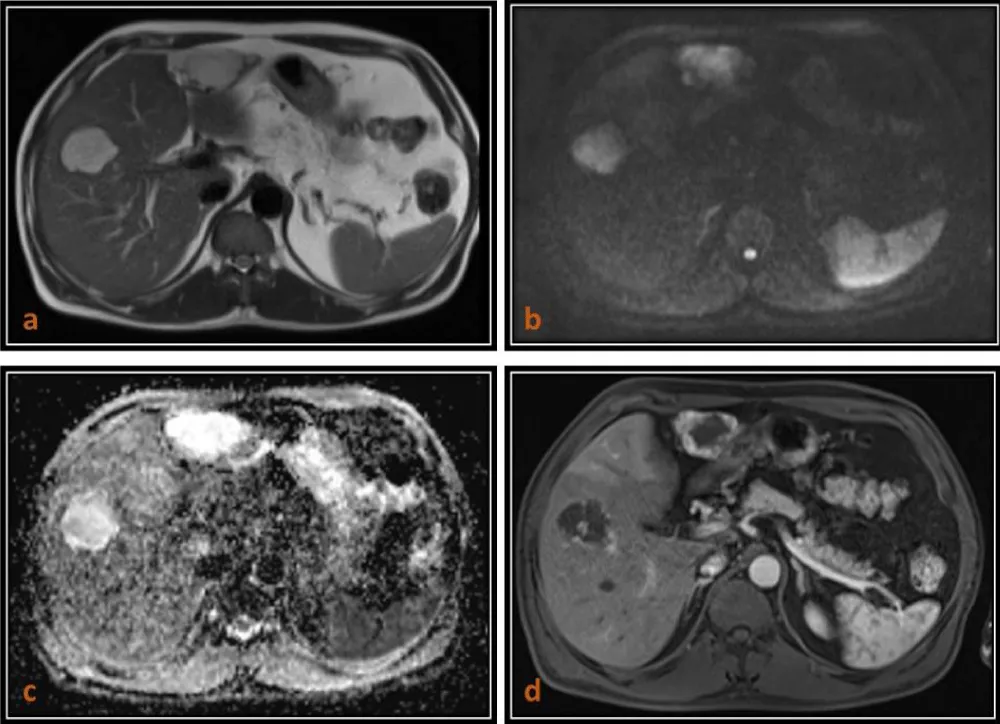

In our study, hepatic cysts demonstrated the highest ADC values, followed by hemangiomas, whereas malignant lesions such as HCC and metastases showed significantly lower ADC values. The mean ADC values of malignant lesions were significantly lower (0.90 ± 0.15 × 10-3 mm2/s) (Figures 1,2,4) than those of benign lesions (2.19 ± 0.29 × 10-3 mm2/s) (Figure 3), and this difference was statistically significant, in agreement with previous studies [10]. However, no significant difference was observed between primary (0.89 ± 0.15 × 10-3 mm2/s) and metastatic malignant lesions (0.90 ± 0.14 × 10-3 mm2/s), which may be attributed to the relatively small sample size.

Download Image

Figure 4: 66-year-old male patient who is a known case of Carcinoma rectum with metastases to the liver. (a) Axial T2 (HASTE)-weighted image shows two mildly hyperintense lesions in right lobe which are moderately hyperintense on WI (b = 800) images as seen in (b) and areisointense with thin hypointense rim on ADC map with low ADC value (0.91 x 10-3 mm2/s) as seen in (c) and shows heterogenous enhancement on T1 (VIBE) post contrast images as seen in (d).